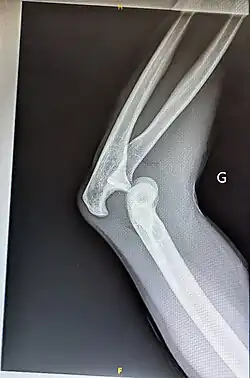

Luxation postérieure du coude gauche sans fracture associée

Luxation du coude

La luxation traumatique du coude est une lésion traumatique non rare, venant en second, derrière la luxation d'épaule.

Elle est habituellement réduite sans retard chez de grands enfants, adolescents ou adultes jeunes.

Une lésion traumatique survenant chez un petit enfant ou un adulte plus âgé est plus vraisemblablement associée à une fracture.

Seule est évoquée, la luxation pure ou seulement associée à un petit fragment osseux périarticulaire.

Traitement

• La réduction du coude est faite sans retard par manipulation externe (en règle pas d'opération).

• Cette réduction « orthopédique » ne pose en règle générale pas de difficulté, volontiers sans anesthésie ni même sédation : en douceur.